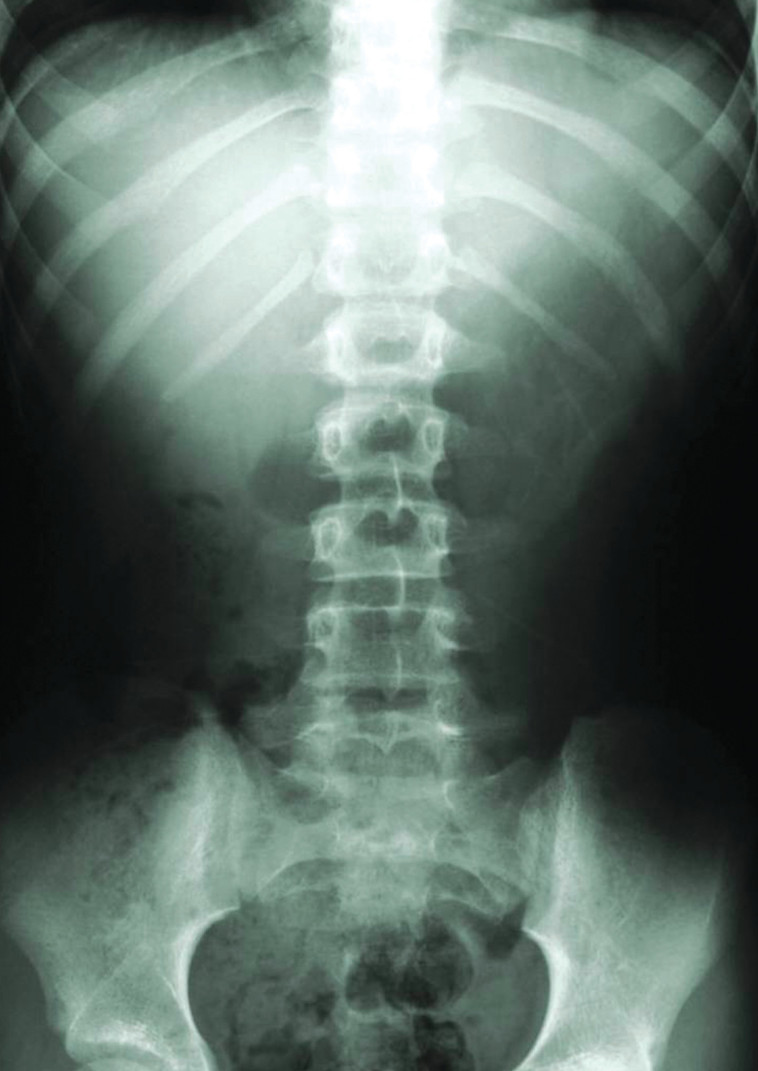

לטענת המומחה, בצילום נראית בבירור הצללה מעוגלת מרכזית באונה העליונה של הריאות עם ממצאים המחשידים לקיומו של גידול. לדבריו, ממצאים אלו מחייבים המשך בירור על ידי בדיקת CT. למרות זאת, מכיוון שתוצאות הפענוח יצאו תקינות, רק כעבור יותר מחצי שנה שבה והתלוננה האישה בפני רופא המשפחה שלה על חולשה ושיעול. היא הופנתה לביצוע צילום חזה חוזר, ורק אז הועלתה לראשונה דרישה לבצע CT חזה וברונכוסקופיה דחופה.

צילום רנטגן. לטענת התובעים, היה ניתן להבחין בגידול בזמן

מומחה ברפואת ריאות מטעם התביעה קבע כי כבר בצילום החזה הראשון שנערך כשנה וחצי לפני מותה של המנוחה, "צריך ואפשר היה כבר לזהות תהליך של סרטן בשלב מוקדם". שבעה חודשים מאוחר יותר אובחן כי הסרטן כבר נמצא בשלב מתקדם. המומחה קבע כי במועד שבו אפשר היה לזהות את המחלה, אפשר היה לטפל בה "בטיפול יעיל, וכי האיחור באבחון המחלה לא הותיר למנוחה סיכוי לריפוי".